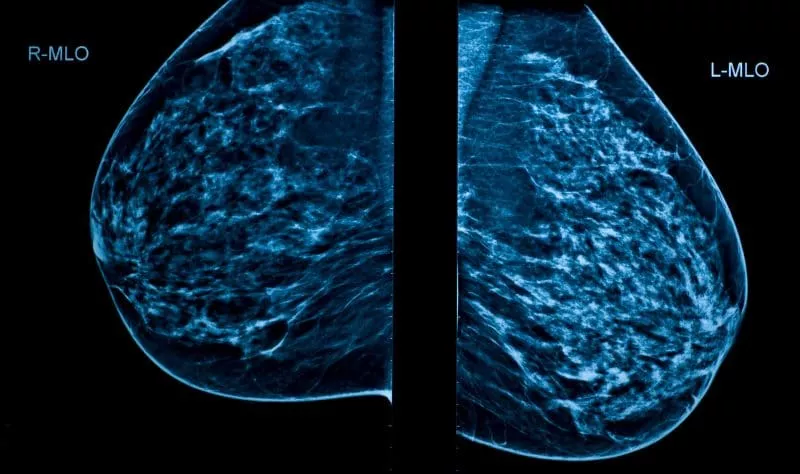

Radiologists and AI Mammogram Tools: What’s Next in Screening?